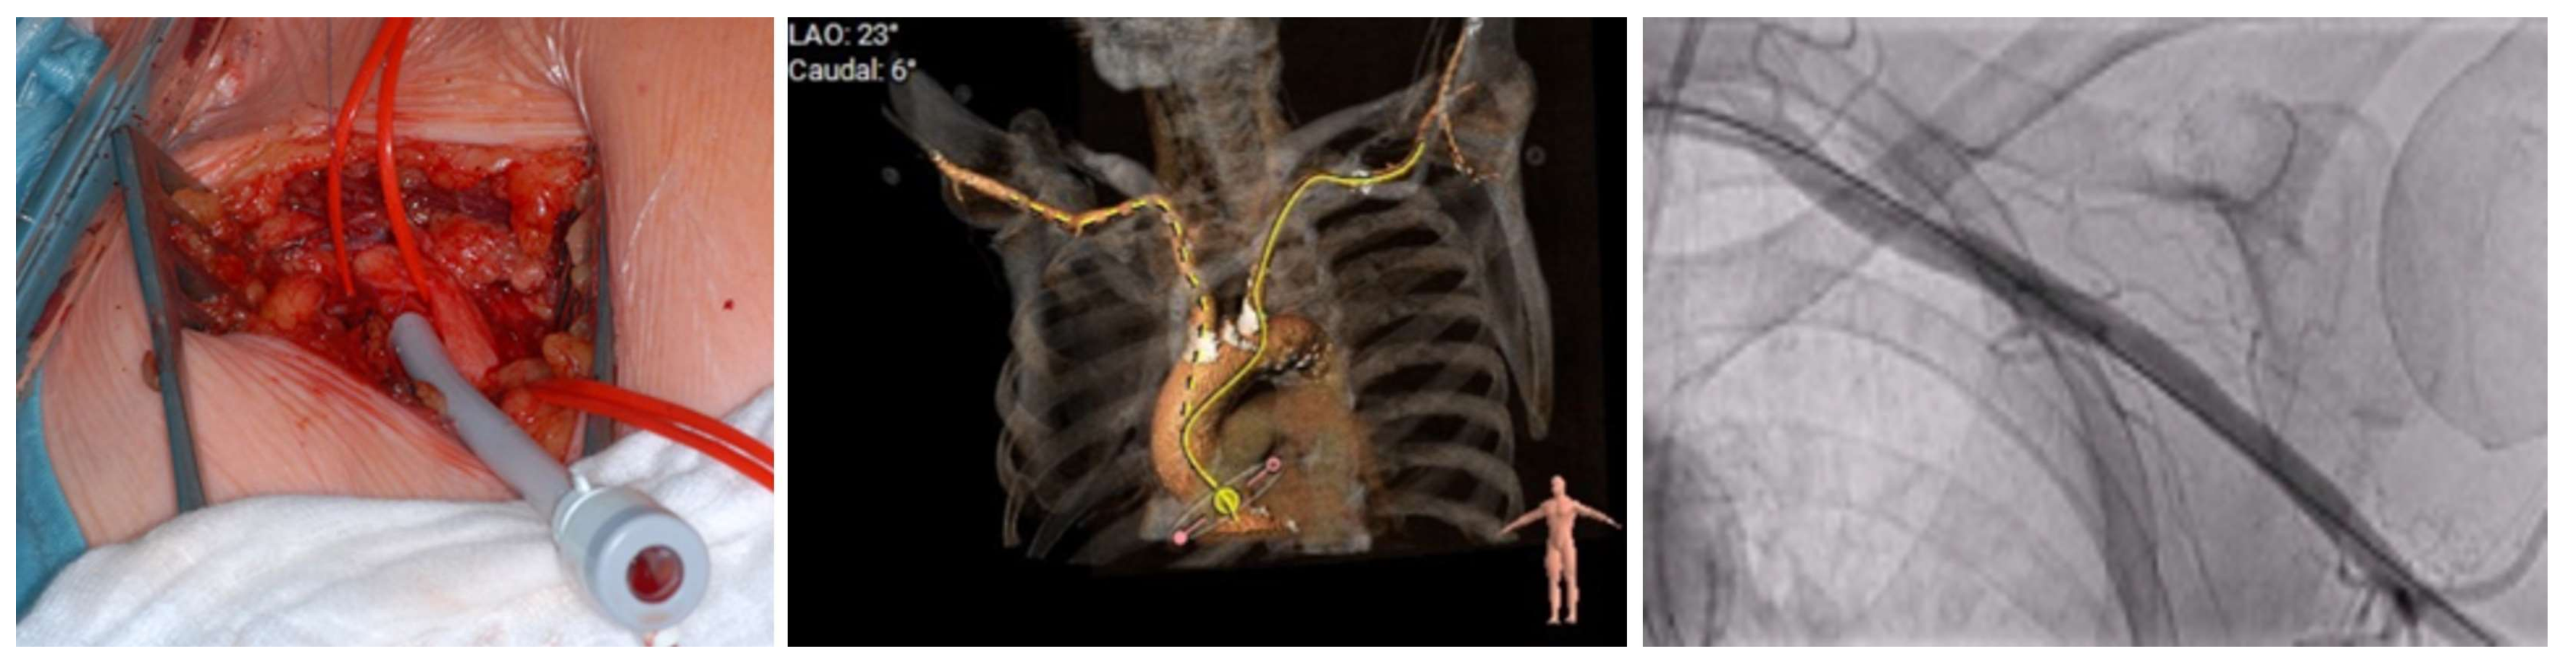

4.2. Procedural Characteristics